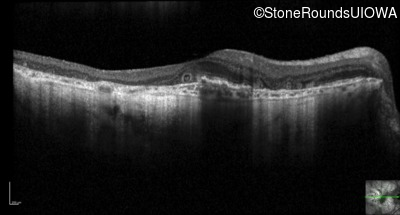

Optical Coherence Tomography - Right - 20/40 -2 sc

Exemplar / OCT Stack